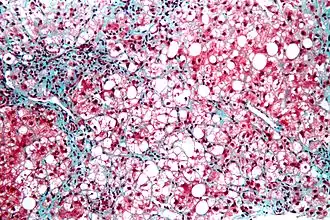

Микрофотография стеатогепатита. Биопсия печени | |